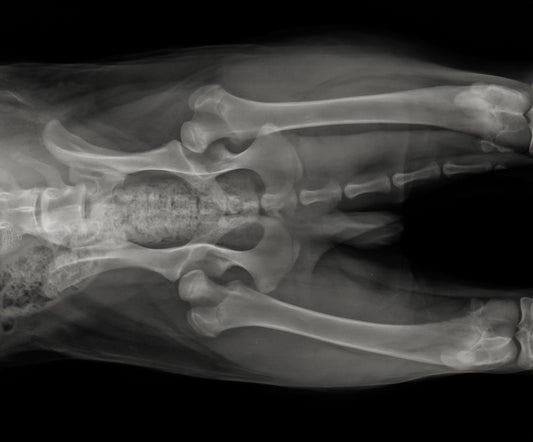

Emma Chandley BVetMed PGCertSAS MRCVS Introduction Cruciate disease, commonly known as cranial cruciate ligament (CrCL) disease, is a frequently seen orthopaedic issue that affects our dog's knee joints. This...